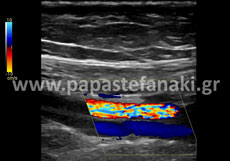

Triplex αγγείων

Για τα Triplex

• Καρωτίδων και σπονδυλικών αρτηριών

• Αρτηριών άνω και κάτω άκρων

• Φλεβών άνω και κάτω άκρων

• Οσχέου

Δεν απαιτείται προετοιμασία.

Ενώ για τα Triplex

• Νεφρικών αρτηριών

• Πυλαίας φλέβας (σπληνοπυλαίου άξονα)

• Κοιλιακής αορτής

• Λαγονίων αρτηριών

• Έλεγχος και παρακολούθηση θεραπευτικών επεμβάσεων (παρακαμπτήρια μοσχεύματα, stent) διαφόρων αγγείων στην κοιλιά

Η προετοιμασία του ασθενούς είναι απαραίτητη.

Πρέπει να είστε νηστικός-ή τουλάχιστον έξι ώρες πριν την εξέταση.

Είναι καλό από την προηγουμένη μέρα να αποφύγετε τροφές με κυτταρίνη, όπως χόρτα, όσπρια, λαχανικά και φρούτα, καθώς και γαλακτοκομικά (γάλα, γιαούρτι).

Ελεύθερα κρέας, ψάρι, κοτόπουλο, ζυμαρικά.

Δεν πρέπει να έχει προηγηθεί την ίδια ημέρα γαστροσκόπηση, ορθοσκόπηση, εξέταση στομάχου ή εντέρου.